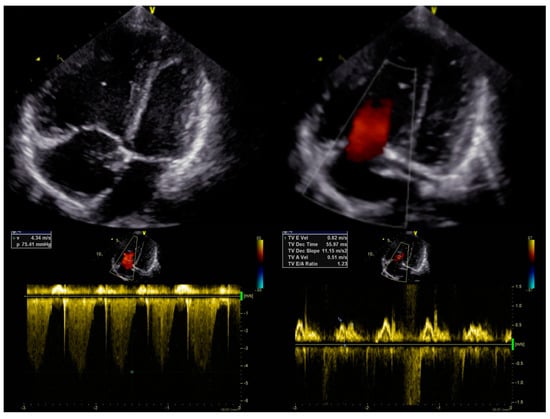

After the introduction of triple therapy, the patient underwent successful BLTx from a cytomegalovirus-positive donor in a referral transplant centre in Vienna. A cytological analysis of the postoperative material after bilateral lung transplantation finally excluded PVOD. Cardiac remodelling occurs early after BLTx as a result of a decreased RV afterload and elevated left ventricular volume preload due to the patient’s healthy lung vasculature and parenchyma of the graft [7]. The two-year follow-up was uneventful, with no signs of PH. In our patient, the echocardiography showed a progressive and rapid recovery of RV function without signs of tricuspid insufficiency (Figure 3B) and a decrease in the diameter (Figure 3A). The pulmonary artery was without valve insufficiency after transplantation, the mean flow volume (MFV) = 0.72 m/s, and we observed a complete withdrawal of PH features (Figure 3C).

Figure 3. Echocardiography in the follow-up after BLTx. (A)—parasternal long-axis view in the M-mode. (B)—apical four-chamber view with doppler at the tricuspid valve. (C)—parasternal short-axis base view with doppler at the pulmonary valve.